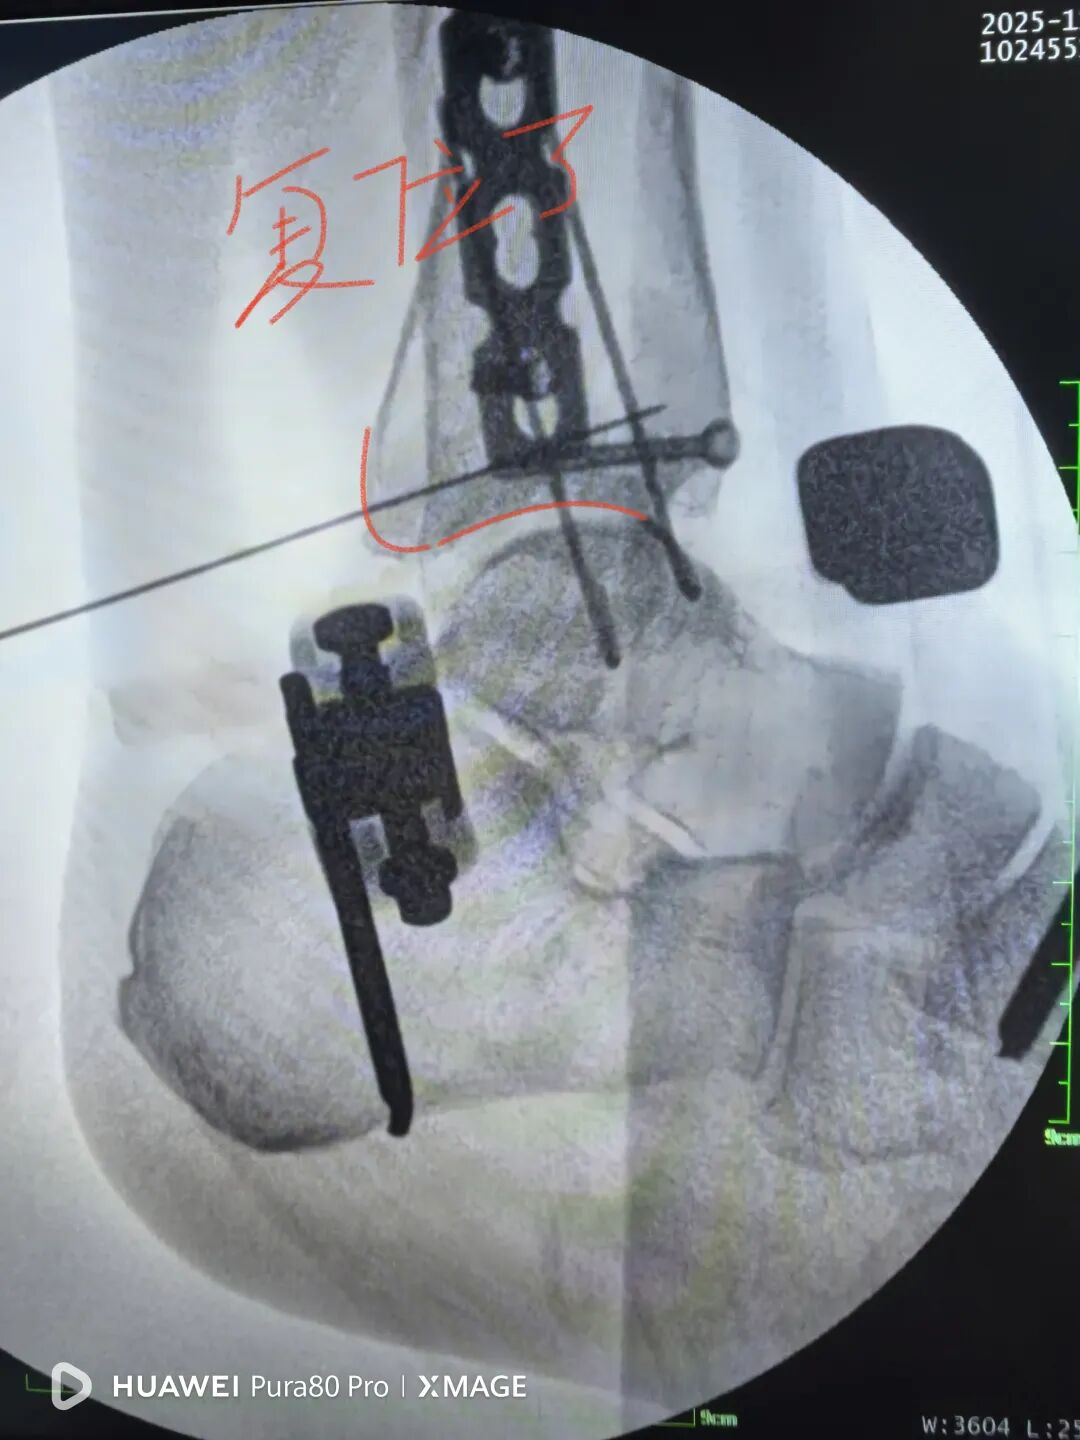

缝合前侧和后外侧切口

取外架

缝合钉道

踝关节被动活动良好